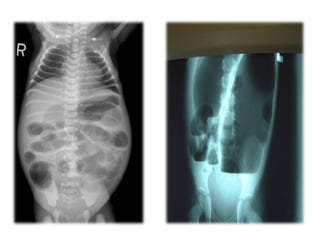

1. Plain x-rays of the abdomen :Erect & supine

2. Contrast enema

– contrast enema should be done without preparation

of bowel

– Shows narrow distal segment,

– funnel-shaped dilatation at level of transition zone

with marked dilatation of the proximal colon.

Investigations Radiology 1.Plain x-rays of the abdomen :Erect & supine 2. Contrast enema – contrast enema should be done without preparation of bowel – Shows narrow distal segment, – funnel-shaped dilatation at level of transition zone with marked dilatation of the proximal colon. 24-hrs delayed films (child with psychogenic stool holding)